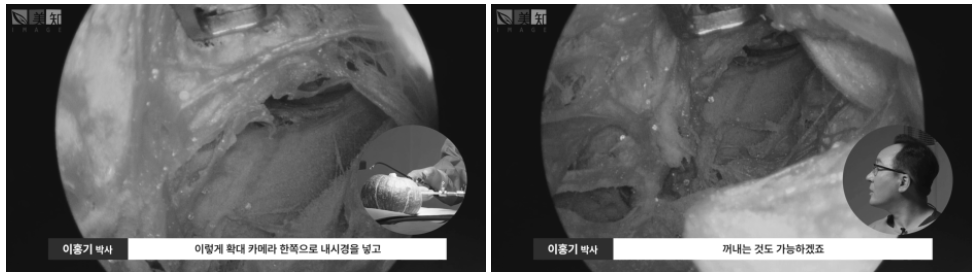

이렇게 확대 카메라 한쪽으로

내시경을 넣고 한쪽으로는

우리 조직을 조작하는 기구를 넣게 되는데

예를 들면 여기에 있는 호박의 씨앗을

이렇게 잡아서 꺼내는 것도 가능하겠죠.

절개하지 않고도 그렇죠.